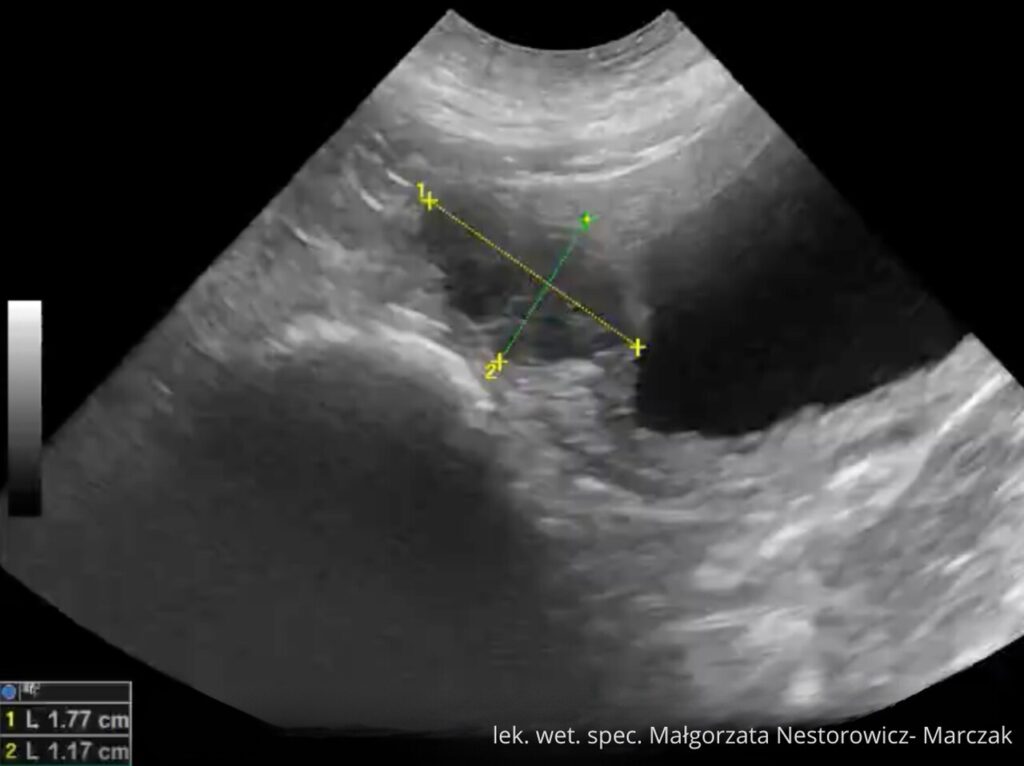

Nauka odbywa się poprzez dostęp do praktycznych nagrań wideo, przygotowanych przez lek. wet. spec. diagnostyki obrazowej Małgorzatę Nestorowicz-Marczak w oparciu o jej doświadczenie oraz pracę kliniczną.

lek. wet. spec. Małgorzata Nestorowicz- Marczak

Absolwentka Wydziału Medycyny Weterynaryjnej (2016), członek Sekcji Weterynaryjnej Polskiego Towarzystwa Ultrasonograficznego (SW PTU).

Już na studiach rozpoczęła naukę ultrasonografii poprzez uczestnictwo w licznych seminariach i kursach. W 2020 roku ukończyła międzynarodowy kurs ultrasonografii w ramach ESAVS (Ultrasound II). W czerwcu 2025 roku ukończyła 3-letnie studia podyplomowe z weterynaryjnej diagnostyki obrazowej w Lublinie uzyskując tytuł specjalisty.

Na co dzień pracuje z małymi zwierzętami (psy, koty) w Warszawie wykonując badania USG tkanek miękkich m.in. jamy brzusznej, szyi, klatki piersiowej. Uczestniczy jako prelegent oraz trener części praktycznej w kursach USG organizowanych dla lekarzy weterynarii.